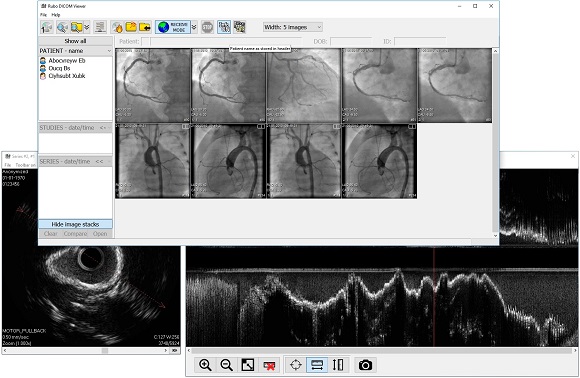

Лазерная камера для печати медицинских изображений на пленке стандарт dicom